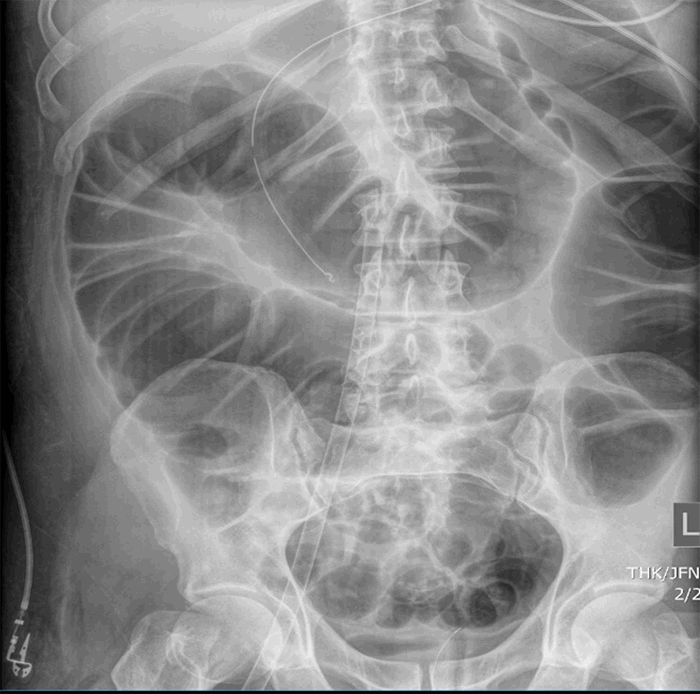

The patient was noted not to be having bowel movements, and his abdomen became progressively distended. An abdominal X ray showed generalized colonic distension up to 8 cm (Figure 2a). Repeat X rays documented progression of the colonic distention up to 10 cm (Figure 2b). His WBC count was 4000 /uL and serum lactate was 0.9 mg/dL. A presumptive diagnosis of acute colonic pseudo-obstruction versus COVID-19 related paralytic colonic ileus was made. A rectal tube was placed, resulting in the evacuation of a large amount of flatus. Soap and water enema were also administered along with an aggressive bowel regimen. Neostigmine use was considered but never administered. Repeat KUB a few days later showed progressive improvement and resolution of the colonic distension (Figure 2c). The patient subsequently continued to improve, was decannulated from ECMO, extubated, and was transferred to the floor. After he was weaned off ECMO, he was started on subcutaneous Lovenox. The patient was subsequently discharged to a post-acute care facility.

Figure 2. Case 2 CT imaging (a) abdominal X-ray showing generalized colonic distension; (b) abdominal X-ray showing progressive colonic distension; (c) abdominal X-ray showing resolution of colonic distension